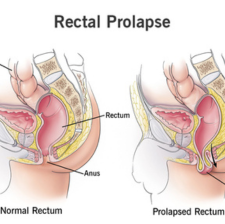

Rectal Prolapse

A condition that occurs when part of the large intestine slips outside the anus.Rectal prolapse typically occurs in older women, but it can occur in men and women of any age. Risk factors include multiple births and vaginal deli.